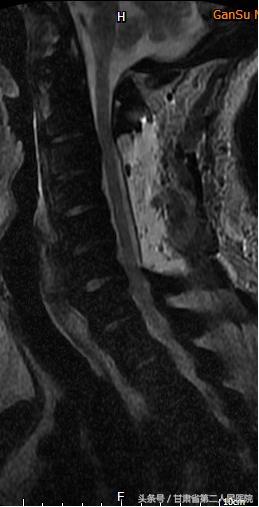

1月25日,省二院骨科袁治国主任、白登彦副主任带领医护团队,在手术麻醉科医护人员的大力配合下,历时5小时,出血不到100ML,顺利完成了“C3-6后路椎板切除钉棒系统内固定术”。

术后,患者麻醉清醒后即感轻松很多。术后2天,患者即能下地行走,好转出院后随访恢复正常。

术后